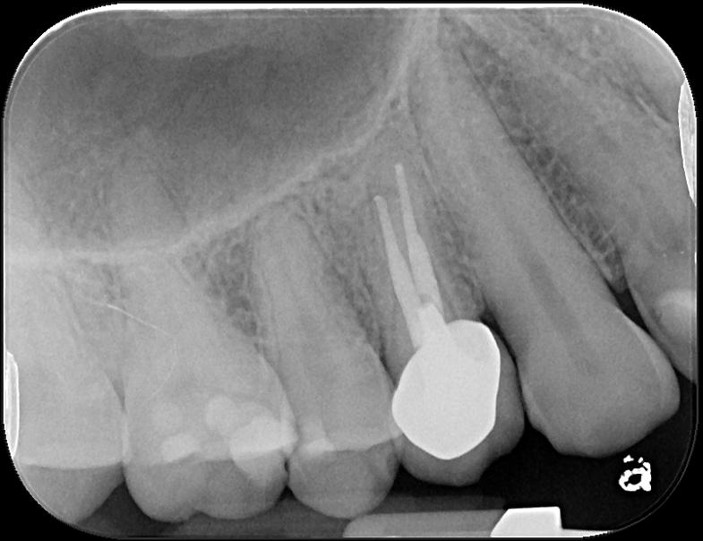

治療前,第一大臼齒根尖病變

顯微根管重治療